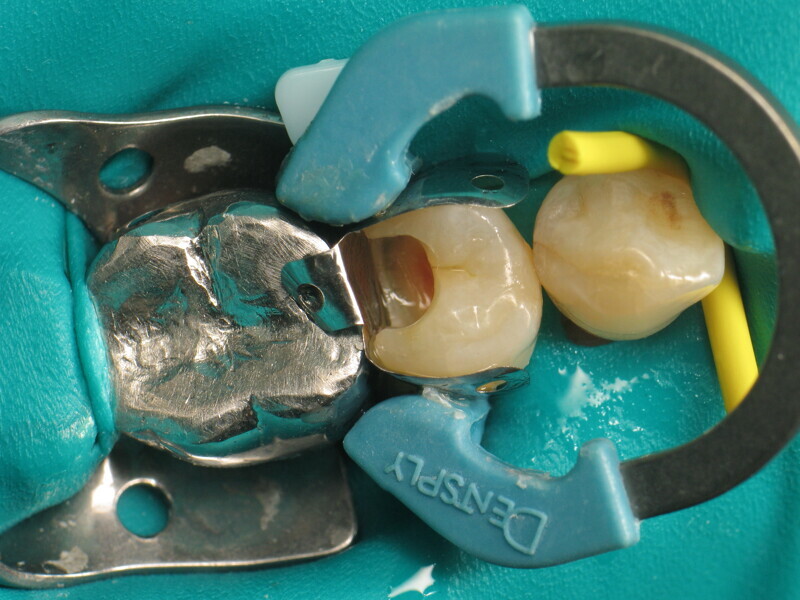

Fig. 1 : Prémolaire avec carie de classe II. (Photos : Yassine Harichane)

Le cas clinique décrit dans cet article porte sur une cavité de classe II sur une prémolaire (45) qui sera restaurée à l’aide d’un composite thermovisqueux (Fig. 1). La dent est isolée avec une digue en latex (Fig. 2). La cavité de classe II est ensuite nettoyée (Fig. 3). Afin d’obtenir une paroi distale anatomiquement correcte, une matrice, un coin et un anneau sont placés (Fig. 4). L’émail dentaire est ensuite mordancé pendant 30 secondes et la dentine pendant 15 secondes (Conditioner 36, Dentsply Sirona ; Fig. 5) puis rincé abondamment (Fig. 6). En raison de la faible épaisseur de dentine restante, une protection pulpaire (Telio Desensitizer, Ivoclar) est également appliquée (Fig. 7). L’adhésif (Futurabond DC, VOCO) est déposé dans la cavité pendant 20 secondes puis séché 5 secondes sous un jet d’air non gras et enfin, photopolymérisé pendant 10 secondes (Figs. 8 et 9). Pour un mouillage optimal, le fond de la cavité est recouvert d’un composite fluide extrêmement fin (GrandioSO Light Flow, A3.5, VOCO) et durci en 20 secondes (Figs. 10 et 11).